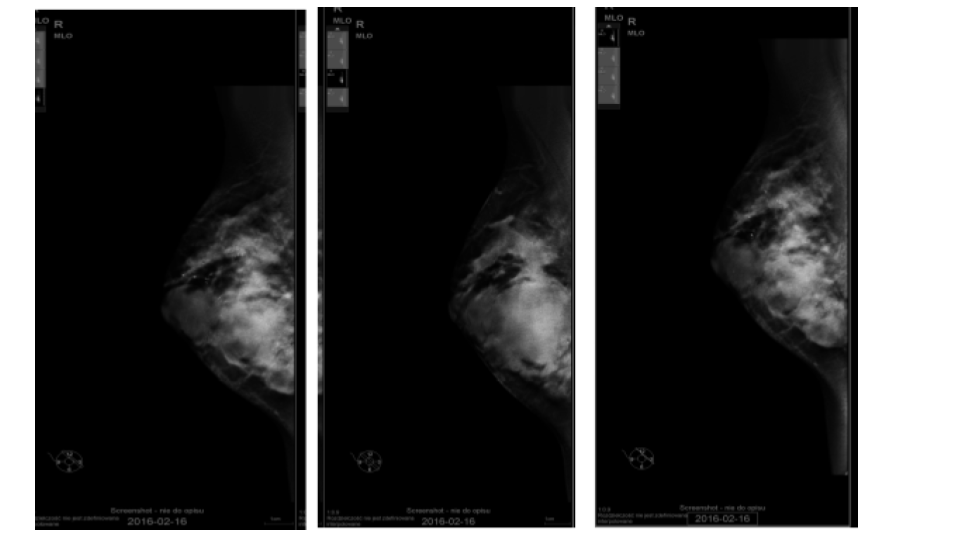

The goal of screening asymptomatic women is to find breast cancer in its earliest stages when treatment has the highest chance for survival. For diagnosis and characterization of primary breast lesions, anatomical imaging such as mammography is the most common screening test for breast cancer, which is basically an x-ray picture of the breast. Examples of mammography images are shown in Fig. 1 for a 67 year old patient. Mammography may find tumors that are too small to feel. It may also find ductal carcinoma in situ (DCIS) [10]. Mammography is more averse to discover breast tumors in women with dense breast tissue. Since both tumors and dense breast tissue seems white on a mammogram, it is hard to find a tumor when there is a dense breast tissue. The mammography sensitivity varies in the range depending on the age of the examined group and number. This range for sensitivity varies from 80% to 96% and in case of specificity it is in the range of 15 to 51.8% [11].